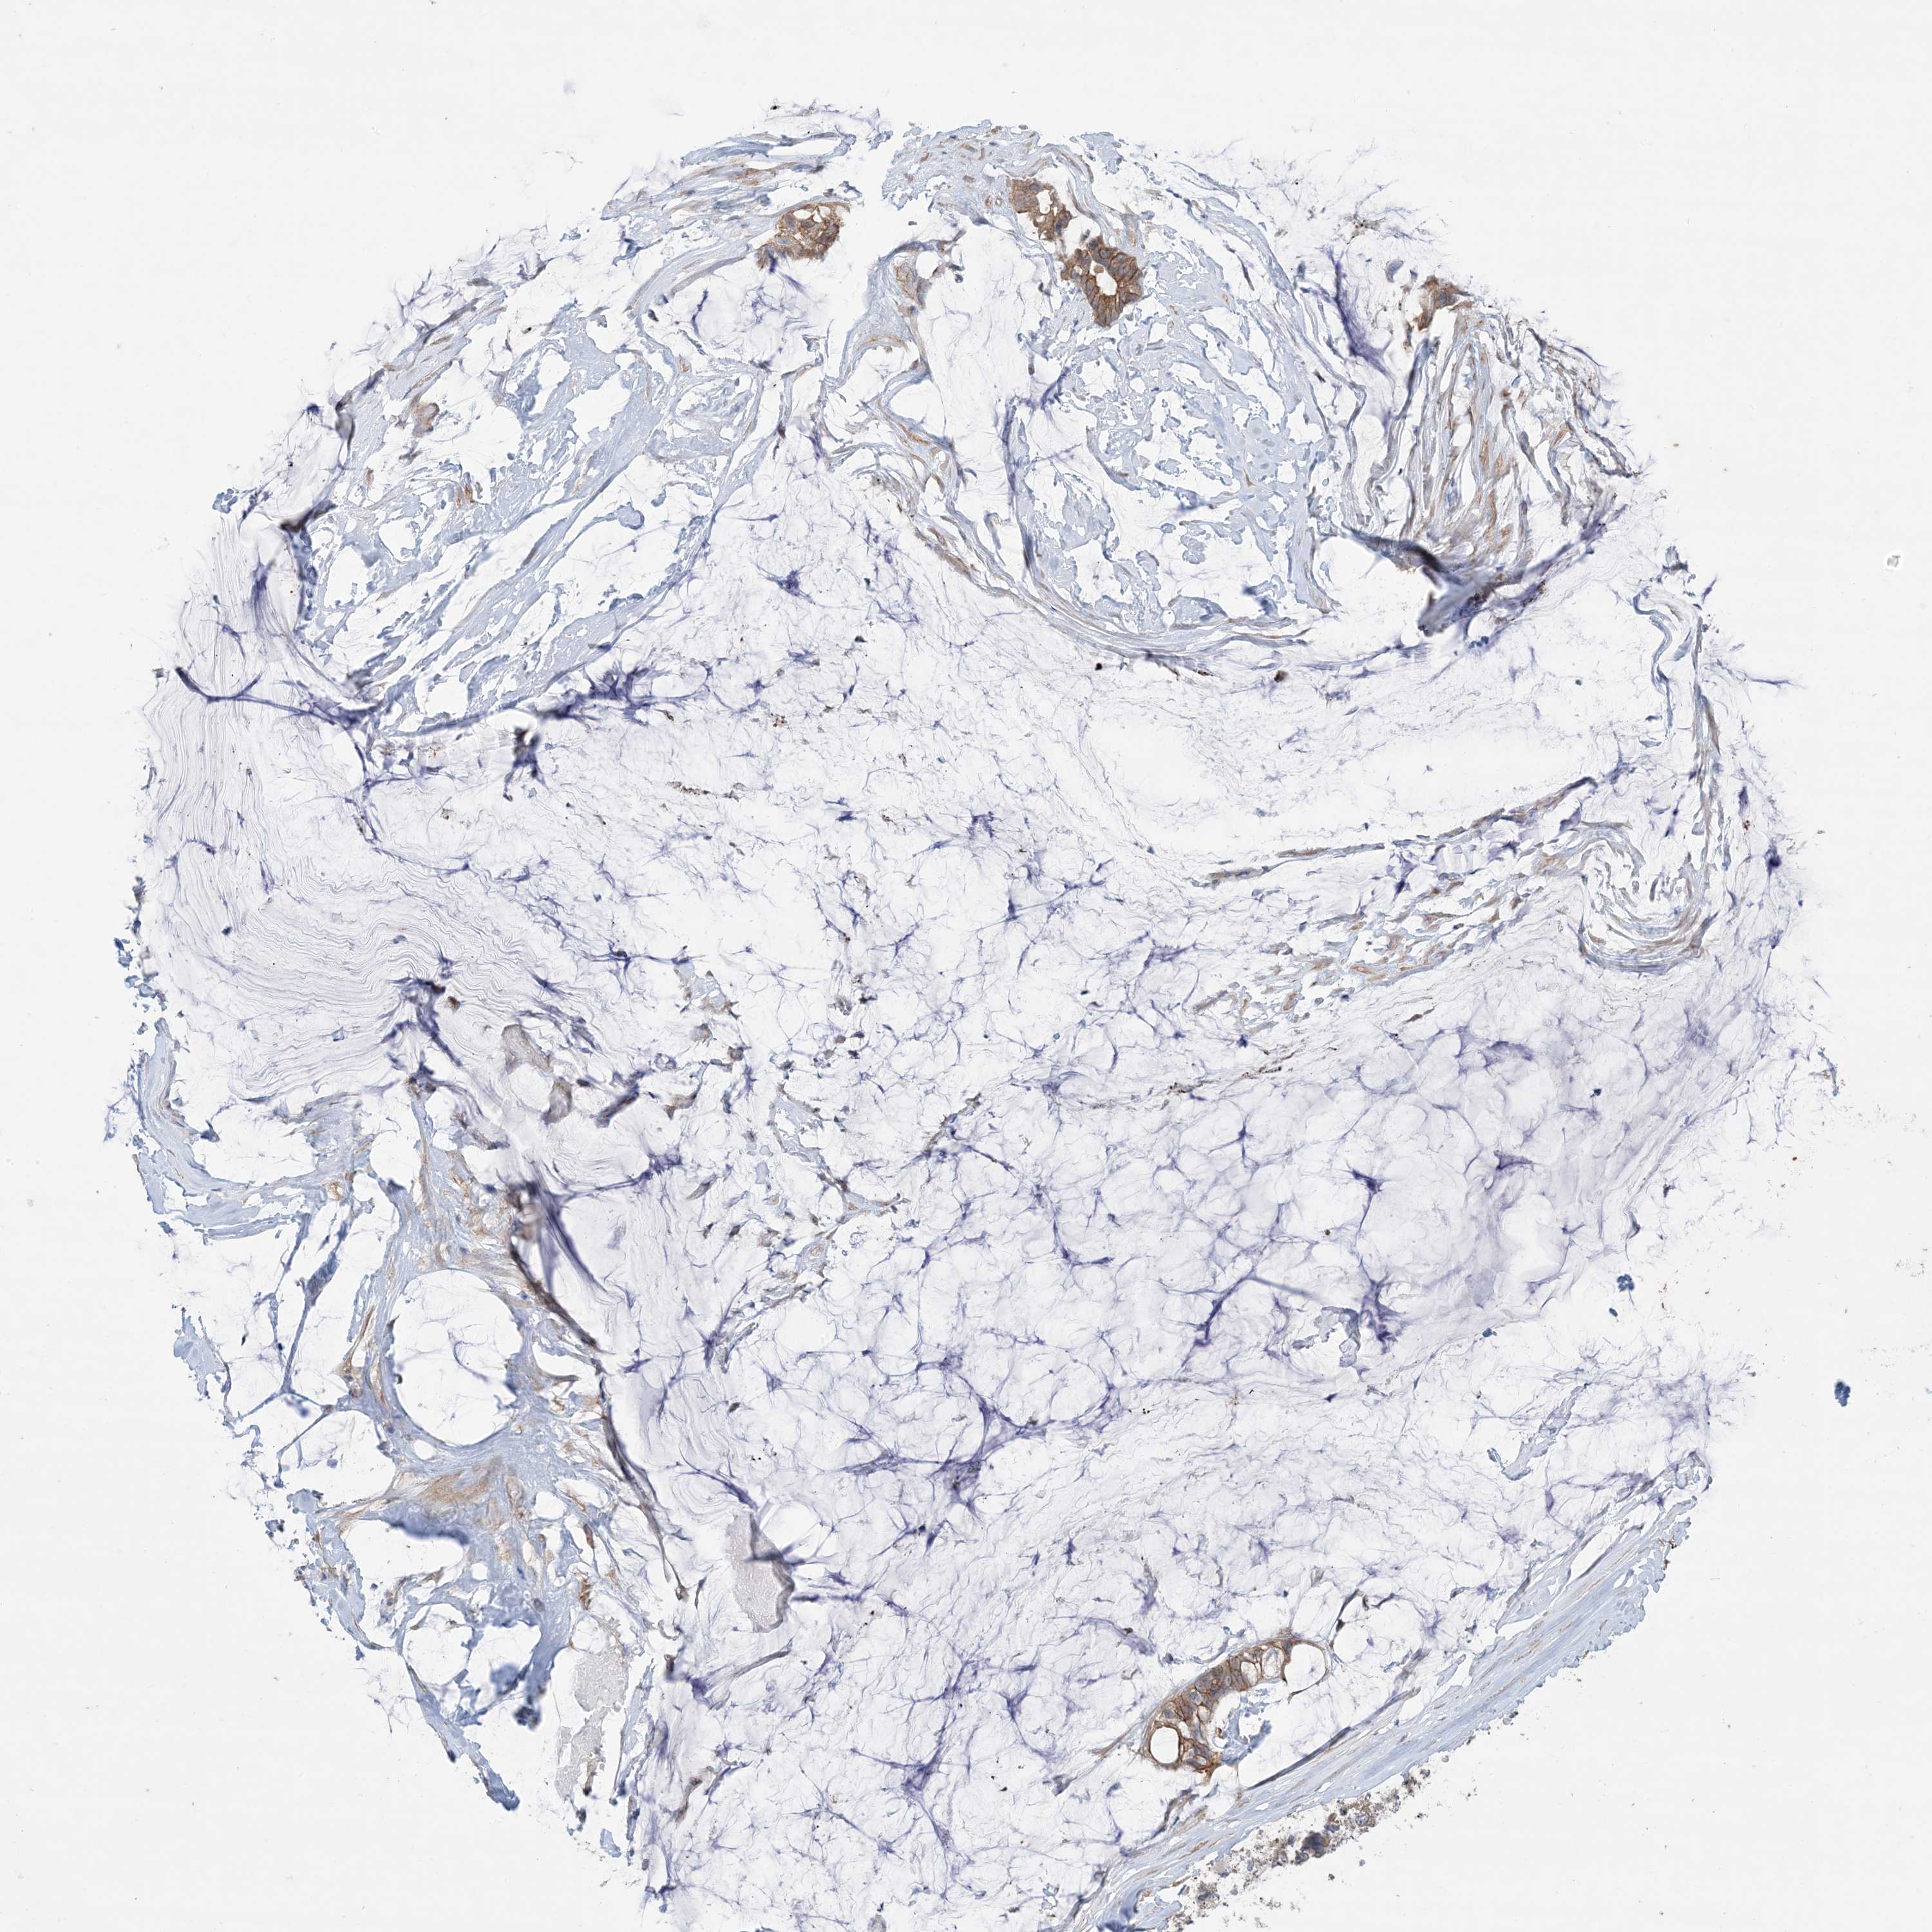

OVARIAN CANCER - Protein expressioni

A mouse-over function shows sample information and annotation data. Click on an image to view it in a full screen mode. Samples can be filtered based on level of antibody staining by selecting one or several of the following categories: high, medium, low and not detected. The assay and annotation is described here.

Note that samples used for immunohistochemistry by the Human Protein Atlas do not correspond to samples in the TCGA dataset.

Antibody stainingi

Antibody staining in the annotated cell types in the current human tissue is reported as not detected, low, medium, or high, based on conventional immunohistochemistry profiling in selected tissues. This score is based on the combination of the staining intensity and fraction of stained cells.

Each image is clickable and will lead to virtual microscopy that enables deeper exploration of all samples and also displays staining intensity scores, fraction scores and subcellular localization as well as patient and tissue information for each sample.

Antibody HPA036290

Staining

High

Medium

Low

Not detected

Intensity

Strong

Moderate

Weak

Negative

Quantity

>75%

75%-25%

<25%

None

Location

Nuclear

Cytoplasmic/membranous

Cytoplasmic/membranous,nuclear

Cystadenocarcinoma, serous, NOS

Carcinoma, endometroid

Cystadenocarcinoma, mucinous, NOS

Carcinoma, NOS